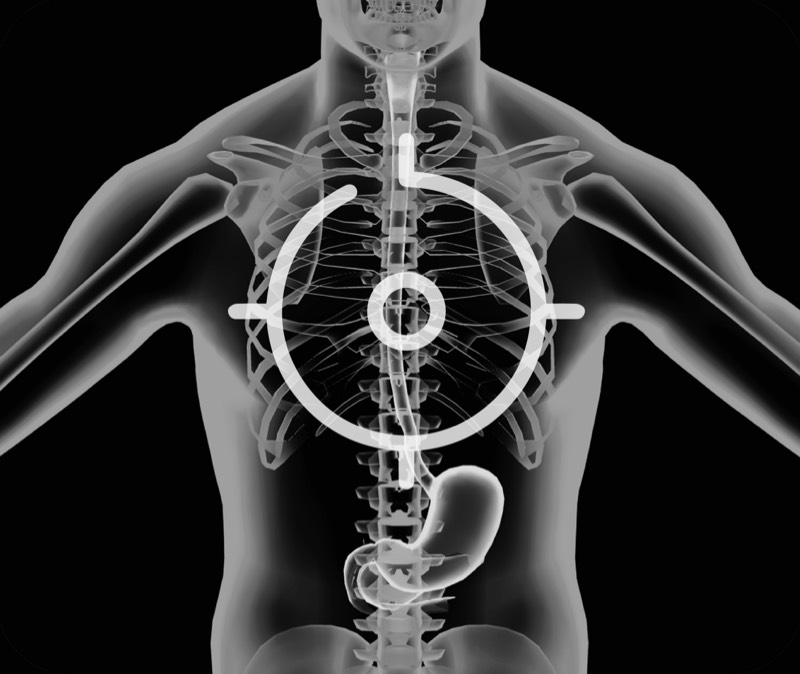

超声电子上消化道内窥镜

360°电子环形扫查与高清内镜影像相结合,提供了良好的插入性能和高清的内镜图像

卓越的宽频设计,满足医生探查不同深度的组织和器官

搭配独立超声主机,为临床提供更优质的超声画质